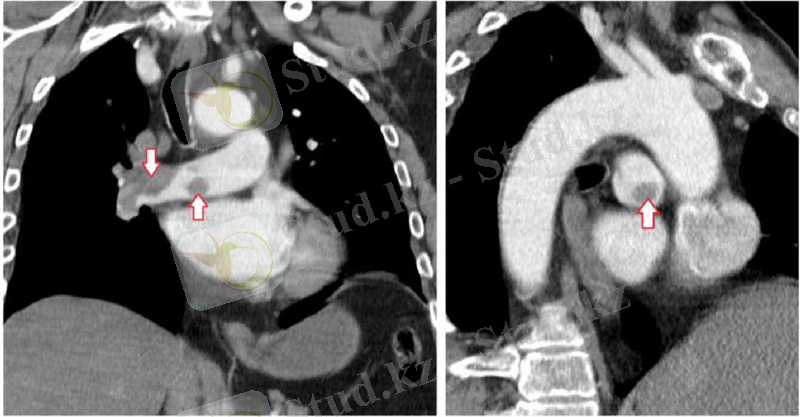

- эхокардиография (өкпе артериясында қысымның жоғарылауын анықтау үшін, дұрыс жүректің шамадан тыс жүктелуі, Жүректің қуысында қан ұюы)

- ангиопульмонография (қан ұйығышының орналасуын және өлшемін дәл анықтау үшін)